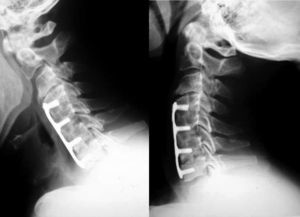

La fusión se consiguió en 18 pacientes (94%) del grupo de cresta ilíaca (fig. 1) y en 12 pacientes (71%) del grupo cajetín de PEEK-aloinjerto (fig. 2). Un paciente del grupo de cresta ilíaca (fig. 3) y 5 pacientes del grupo cajetín-aloinjerto desarrollaron seudoartrosis.